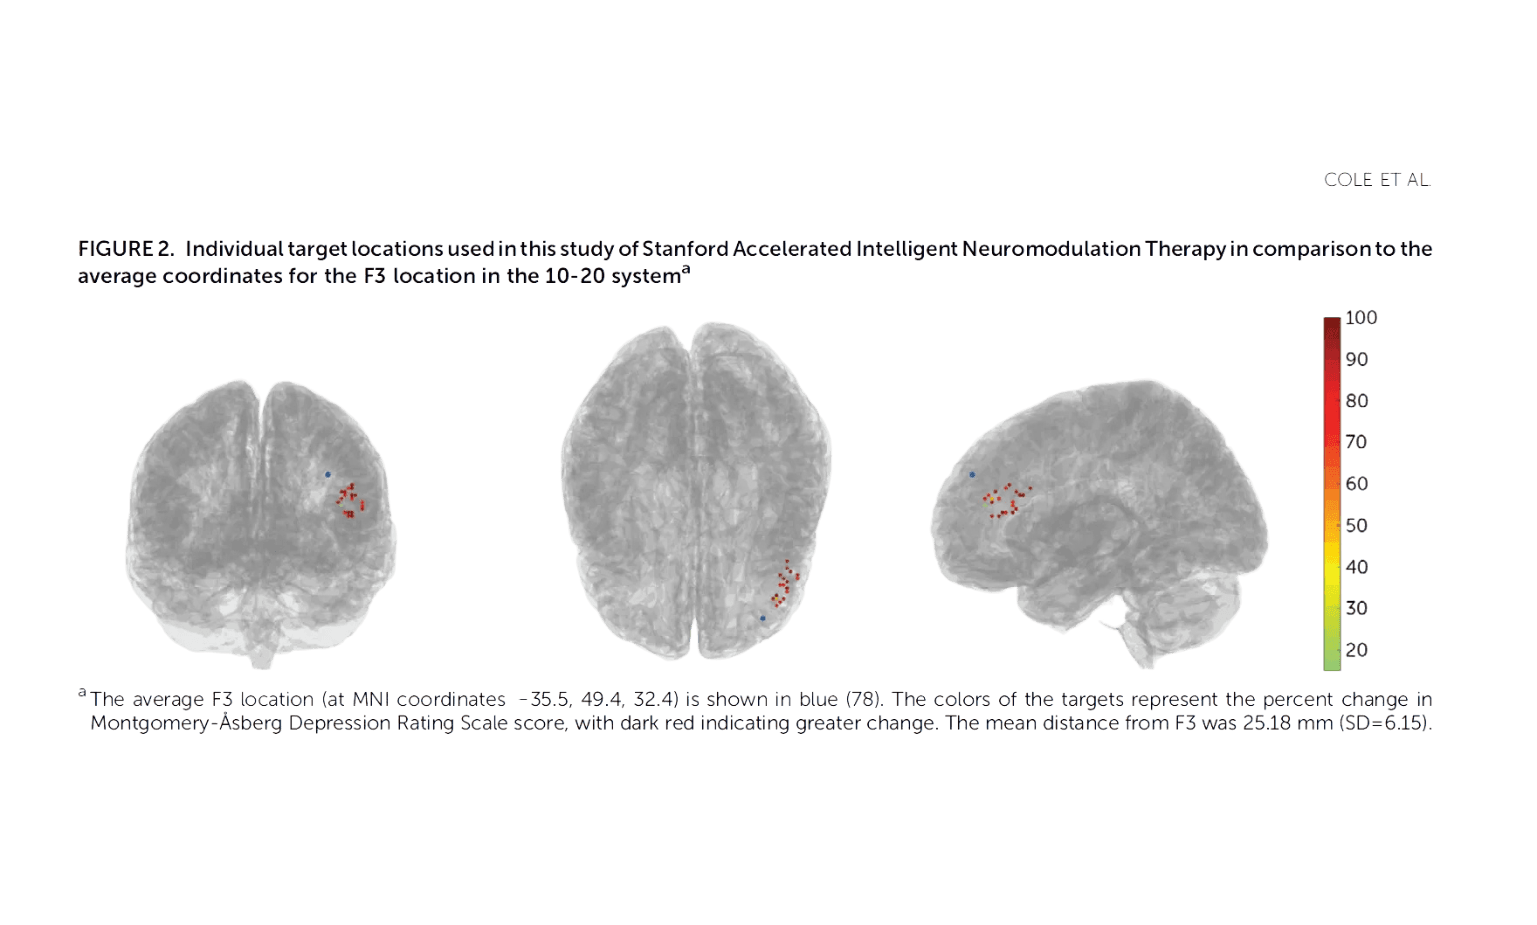

Cole et al Study Graphic via Florida TMS Clinic